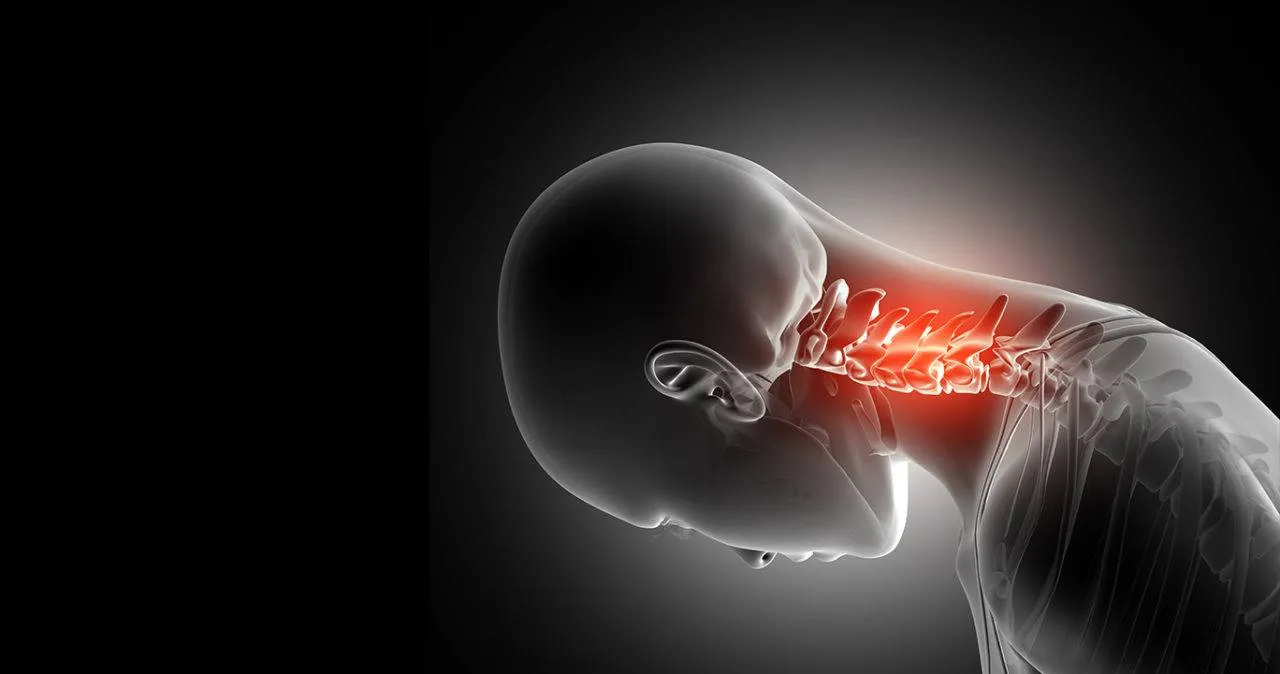

Coluna travada – Região Cervical (pescoço)

Já acordou sem conseguir mover a cabeça para os lados ou para a frente?

Isso é o que nós chamamos de torcicolo.

Sim, a coluna travada nessa região do pescoço cria a sensação de que os músculos podem quebrar se você virar a cabeça e a dor incomoda muito.

O travesseiro pode ser um grande vilão e na maioria das vezes é o culpado pelo pescoço travado.